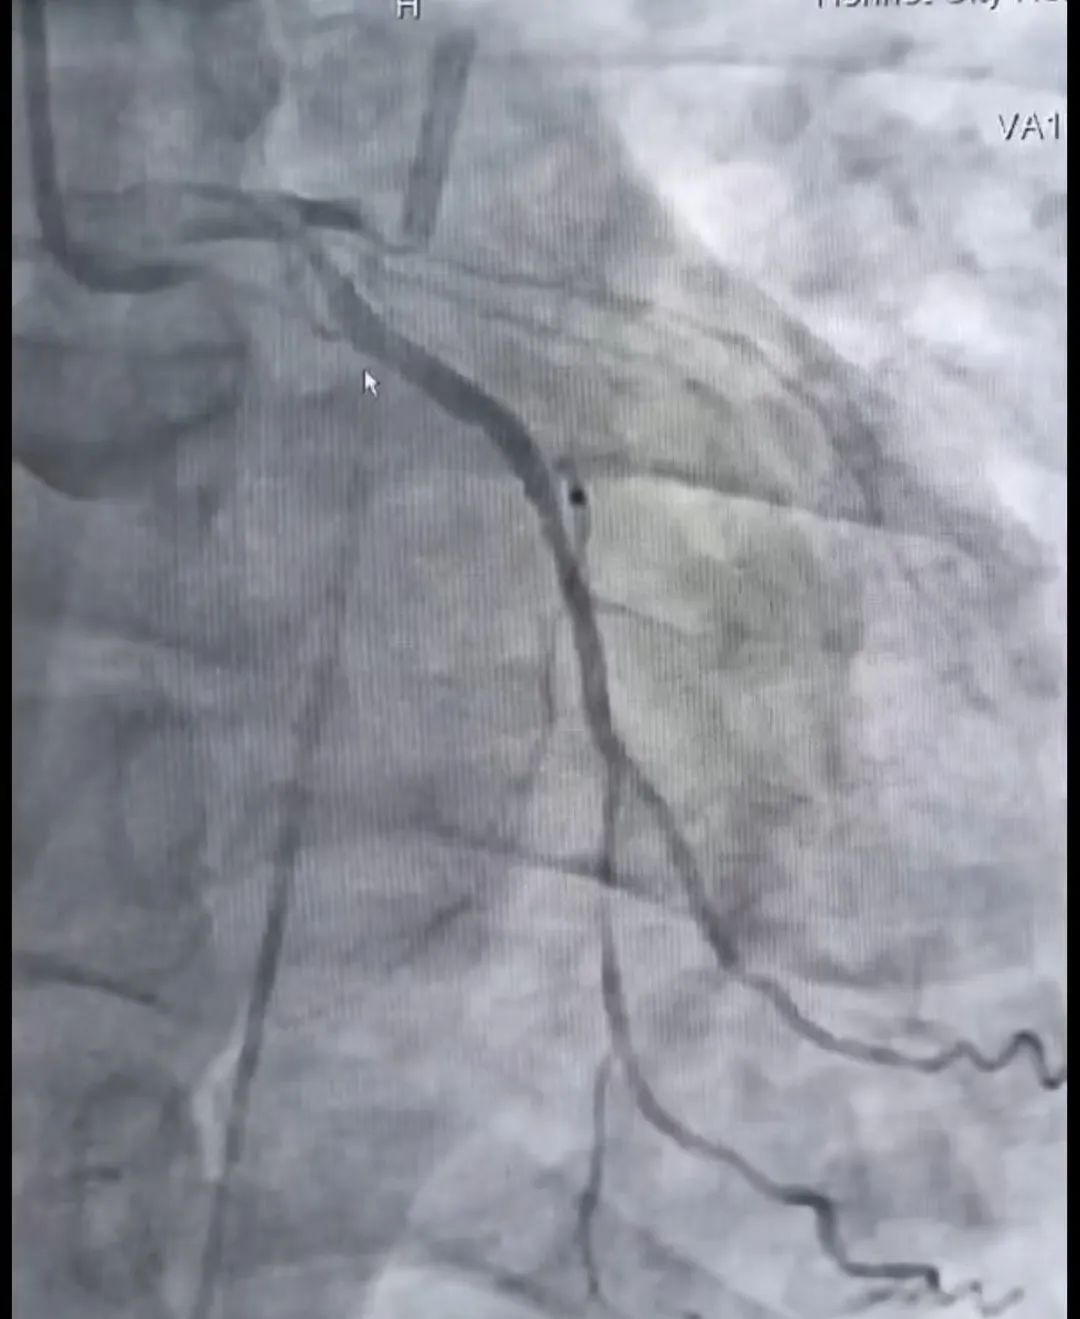

庆幸的是,送入导管室后,患者在经过IABP及药物治疗后可以于半卧位下耐受冠脉介入手术治疗,随后心内科介入团队迅速行冠脉造影,显示前降支急性闭塞、右冠脉慢性闭塞、回旋支中重度狭窄,在与死神百米赛跑的比赛中,团队先快速开通了前降支,解决了罪犯血管,随后又开通了右冠脉,过程中使用血栓抽吸、临时起搏、IVUS、药物球囊植入术等多项操作,于2小时后顺利返回CCU病房。